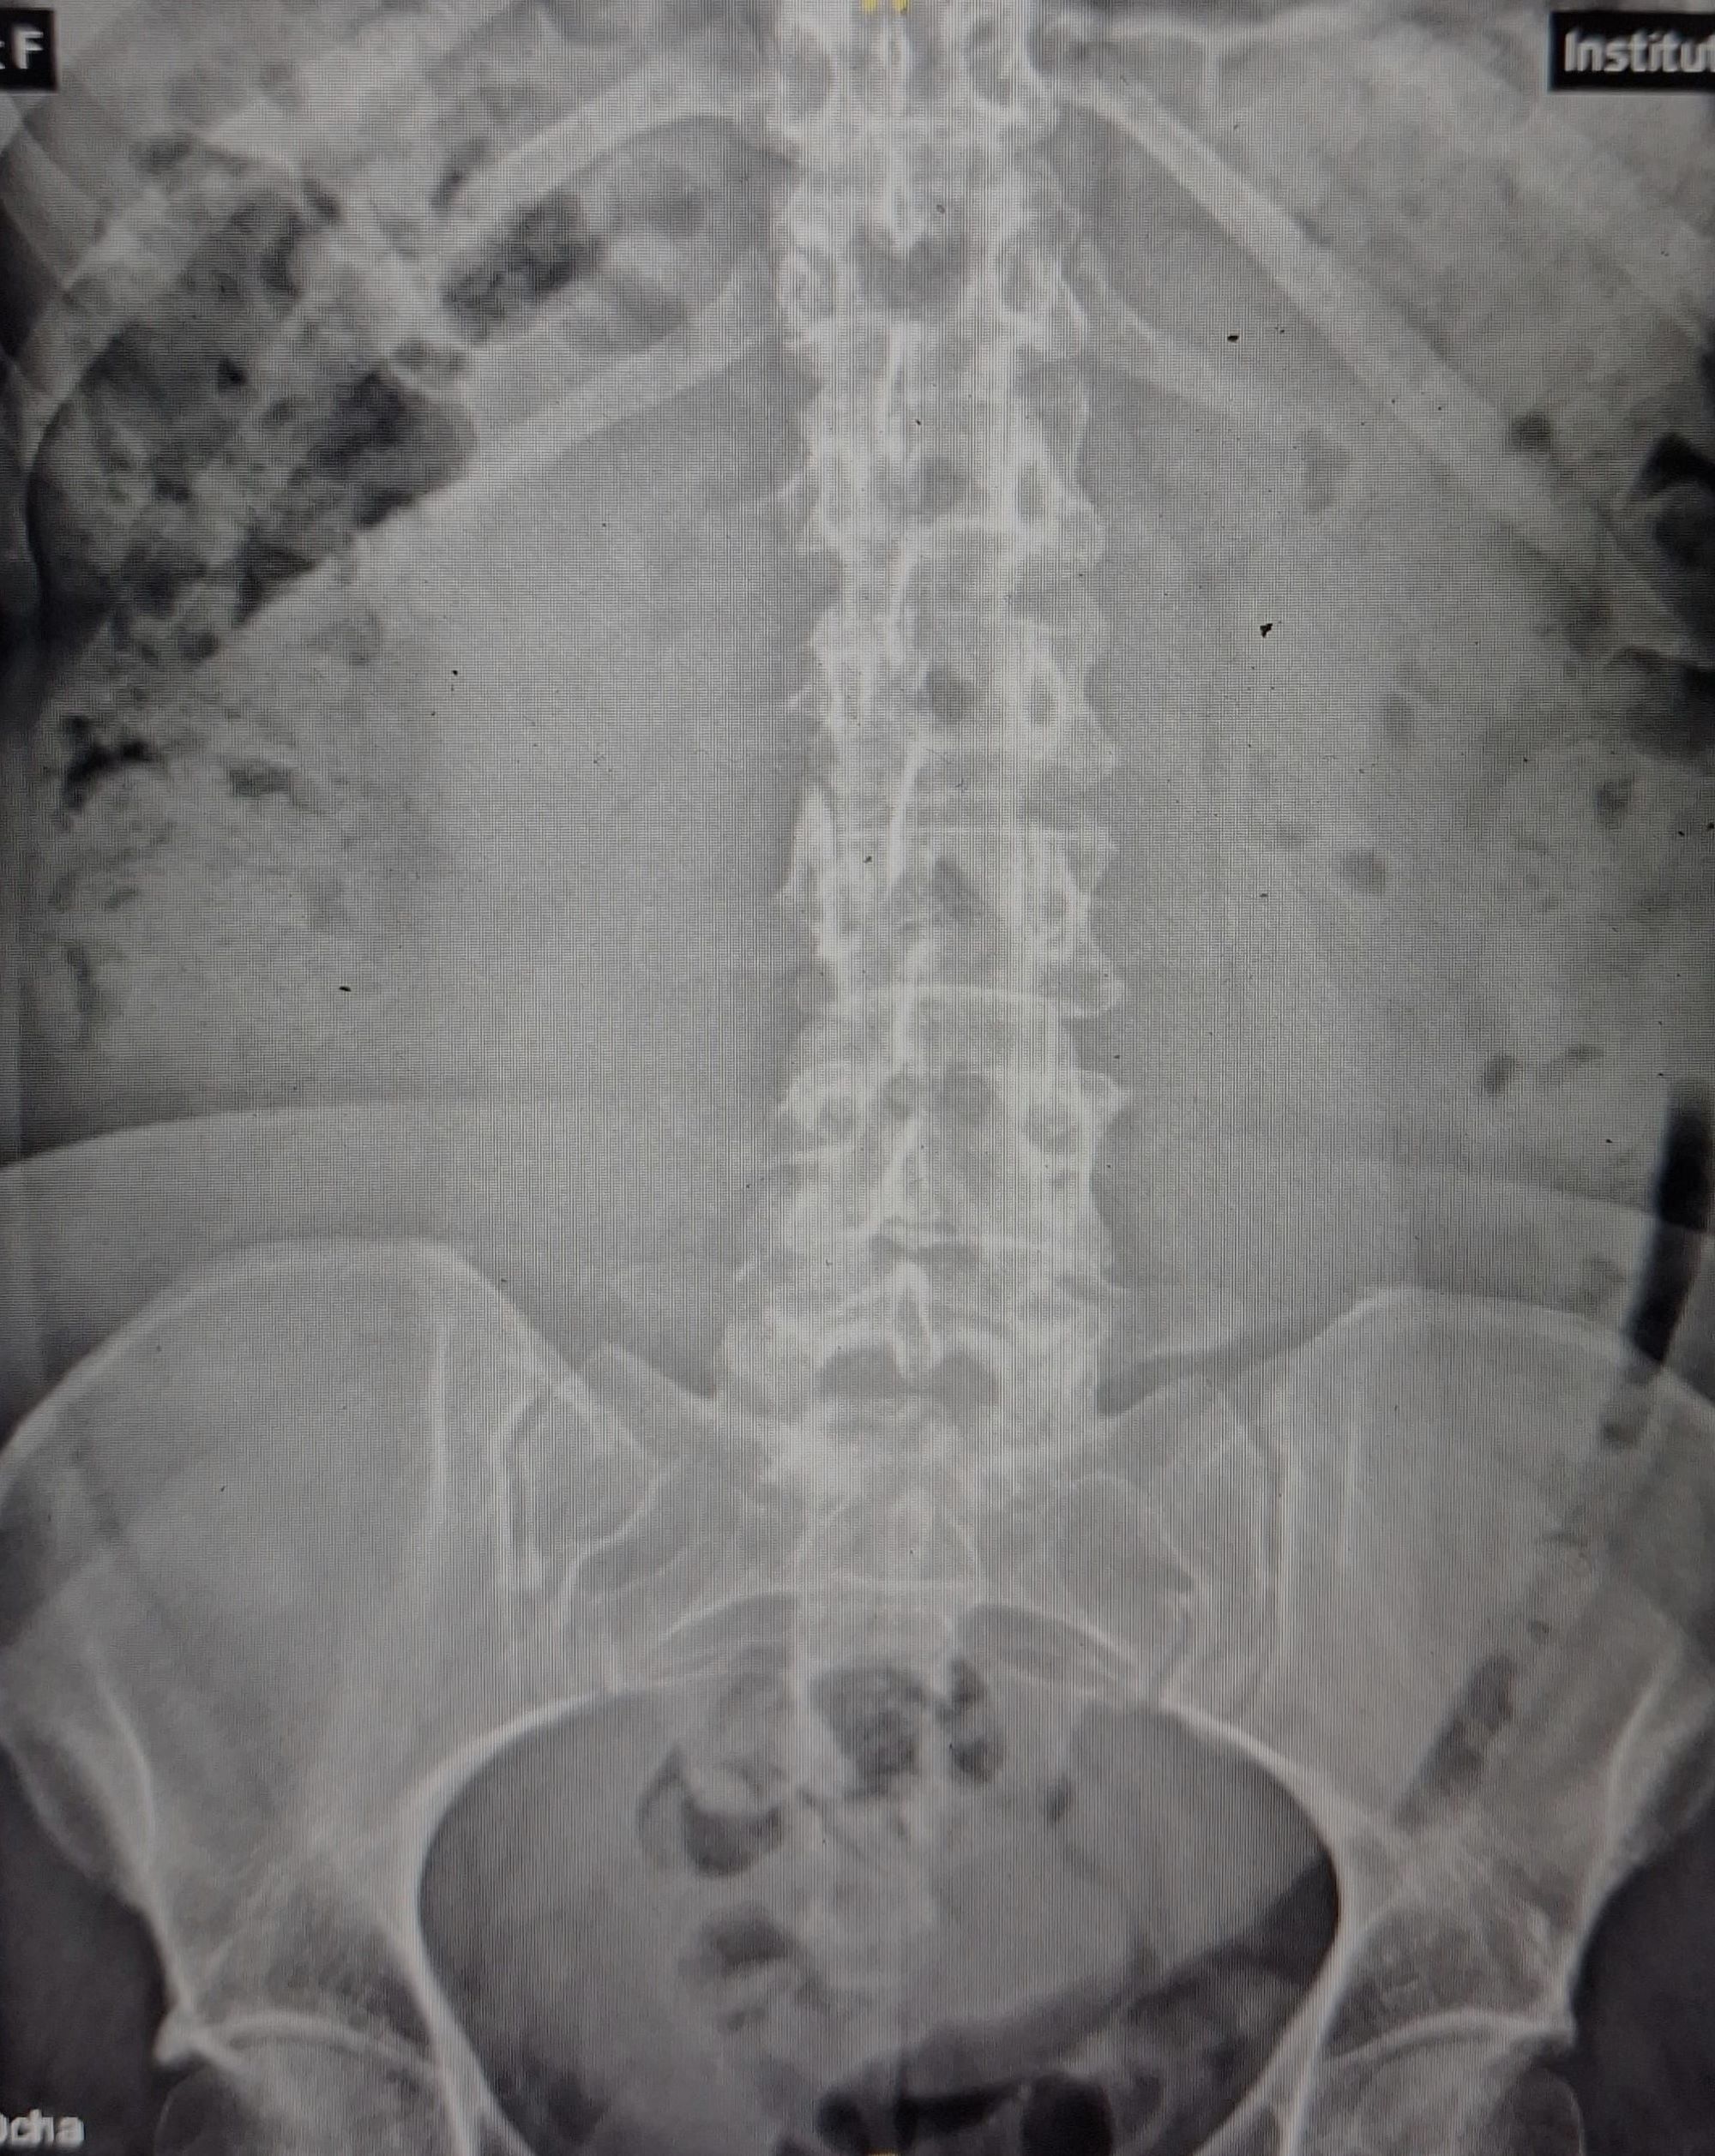

Allí se solicita radiología de abdomen.

Eco abdomen: Masa anecoica con refuerzo posterior de gran tamaño con particulas en su interior, multilobulada y con tabiques en su interior que ocupa desde epigastrio, desplazando al páncreas, hasta mesogastrio, fosas ilíacas e hipogastrio, muy difícil determinar las medidas.

ID: masa de abdomen a estudio.

Diagnóstico diferencial: síndrome de ogilvie, tumor de ovario (cistoadenoma de ovario).